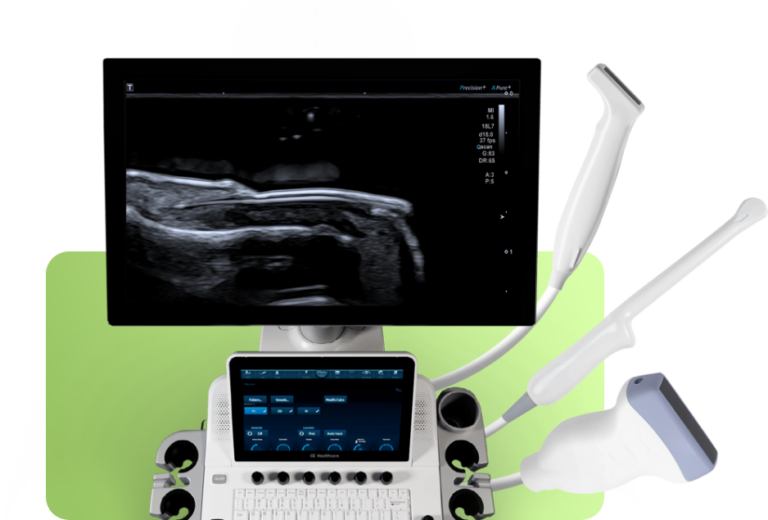

Sou Julia Diva Zavariz, médica radiologista, especialista em ultrassonografia, apaixonada pelo que faço e uma eterna buscadora de conhecimento.

A busca constante pelo aprendizado é um dos pilares da minha trajetória. Acredito que o conhecimento é a chave para o crescimento profissional e pessoal. Muito estudo, cursos, workshops e experiências práticas moldaram minha visão e me permitiram evoluir em minha profissão.